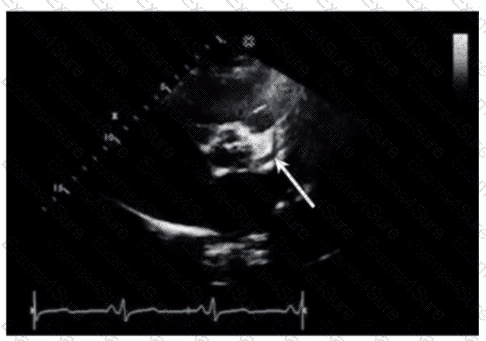

How must the sonographer angle the transducer from the apical four-chamber view in order to visualize the aortic valve in the apical five-chamber view?